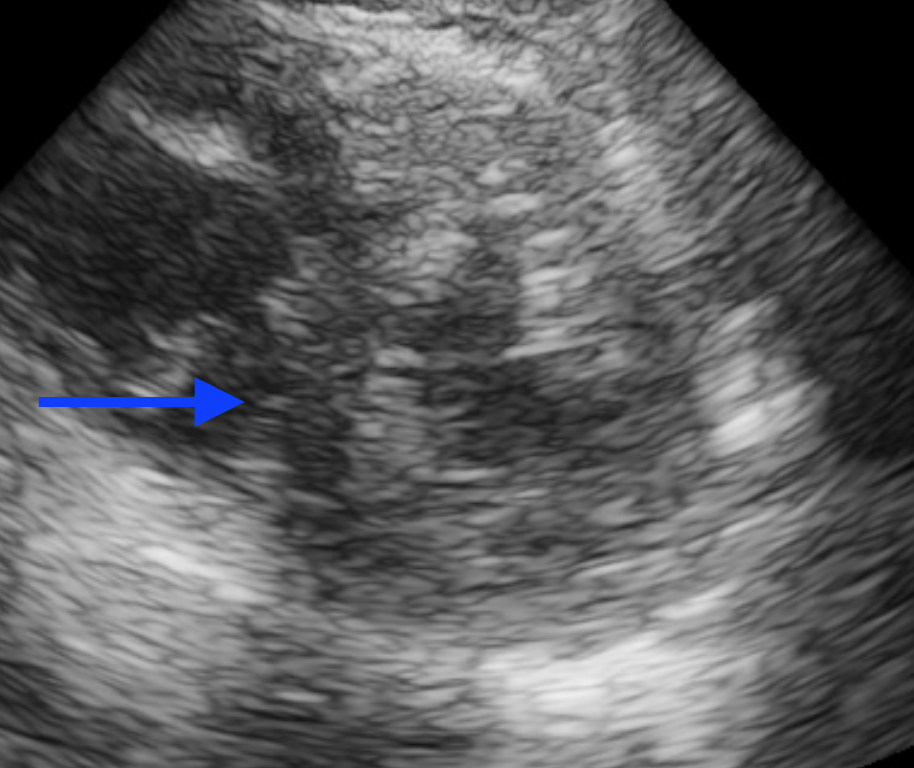

Bedside ultrasound was performed:

In video 1, you can see a hyperdynamic left ventricle. Although you can not tell the size of the right ventricle on the parasternal long, you can see on that the right ventricle dose not seem to have as much motion/squeeze as it normally does. This is indicative of a reduced right ventricular ejection fraction.

In Video 2, although there is not a definitive D sign throughout the entire cardiac cycle, you can actually see signs of right ventricular overload with an intermittent D sign. Watch the septum closely during diastole. You will see that rather than being perfectly round like the donut that it typically looks like in a parasternal short axis, it temporarily becomes a D/bowed in and looks like someone is jumping on a trampoline. This is a sign of right heart strain.

In video 3, you can see the reduced squeeze of the RV and you can also see that the RV is approaching the size of the LV. Normally, the RV should be smaller than the LV. If on an apical 4 chamber view your RV is as large as or larger than your LV, you should be concerned about right heart strain. There is also deviation of the septum on the apical 4 chamber view into the LV which is abnormal and from the RV pressure overload.

Given the above bedside ultrasound, there was concern for PE as the cause of the patient’s hypoxia. CTA was obtained and showed bilateral segmental PE’s.